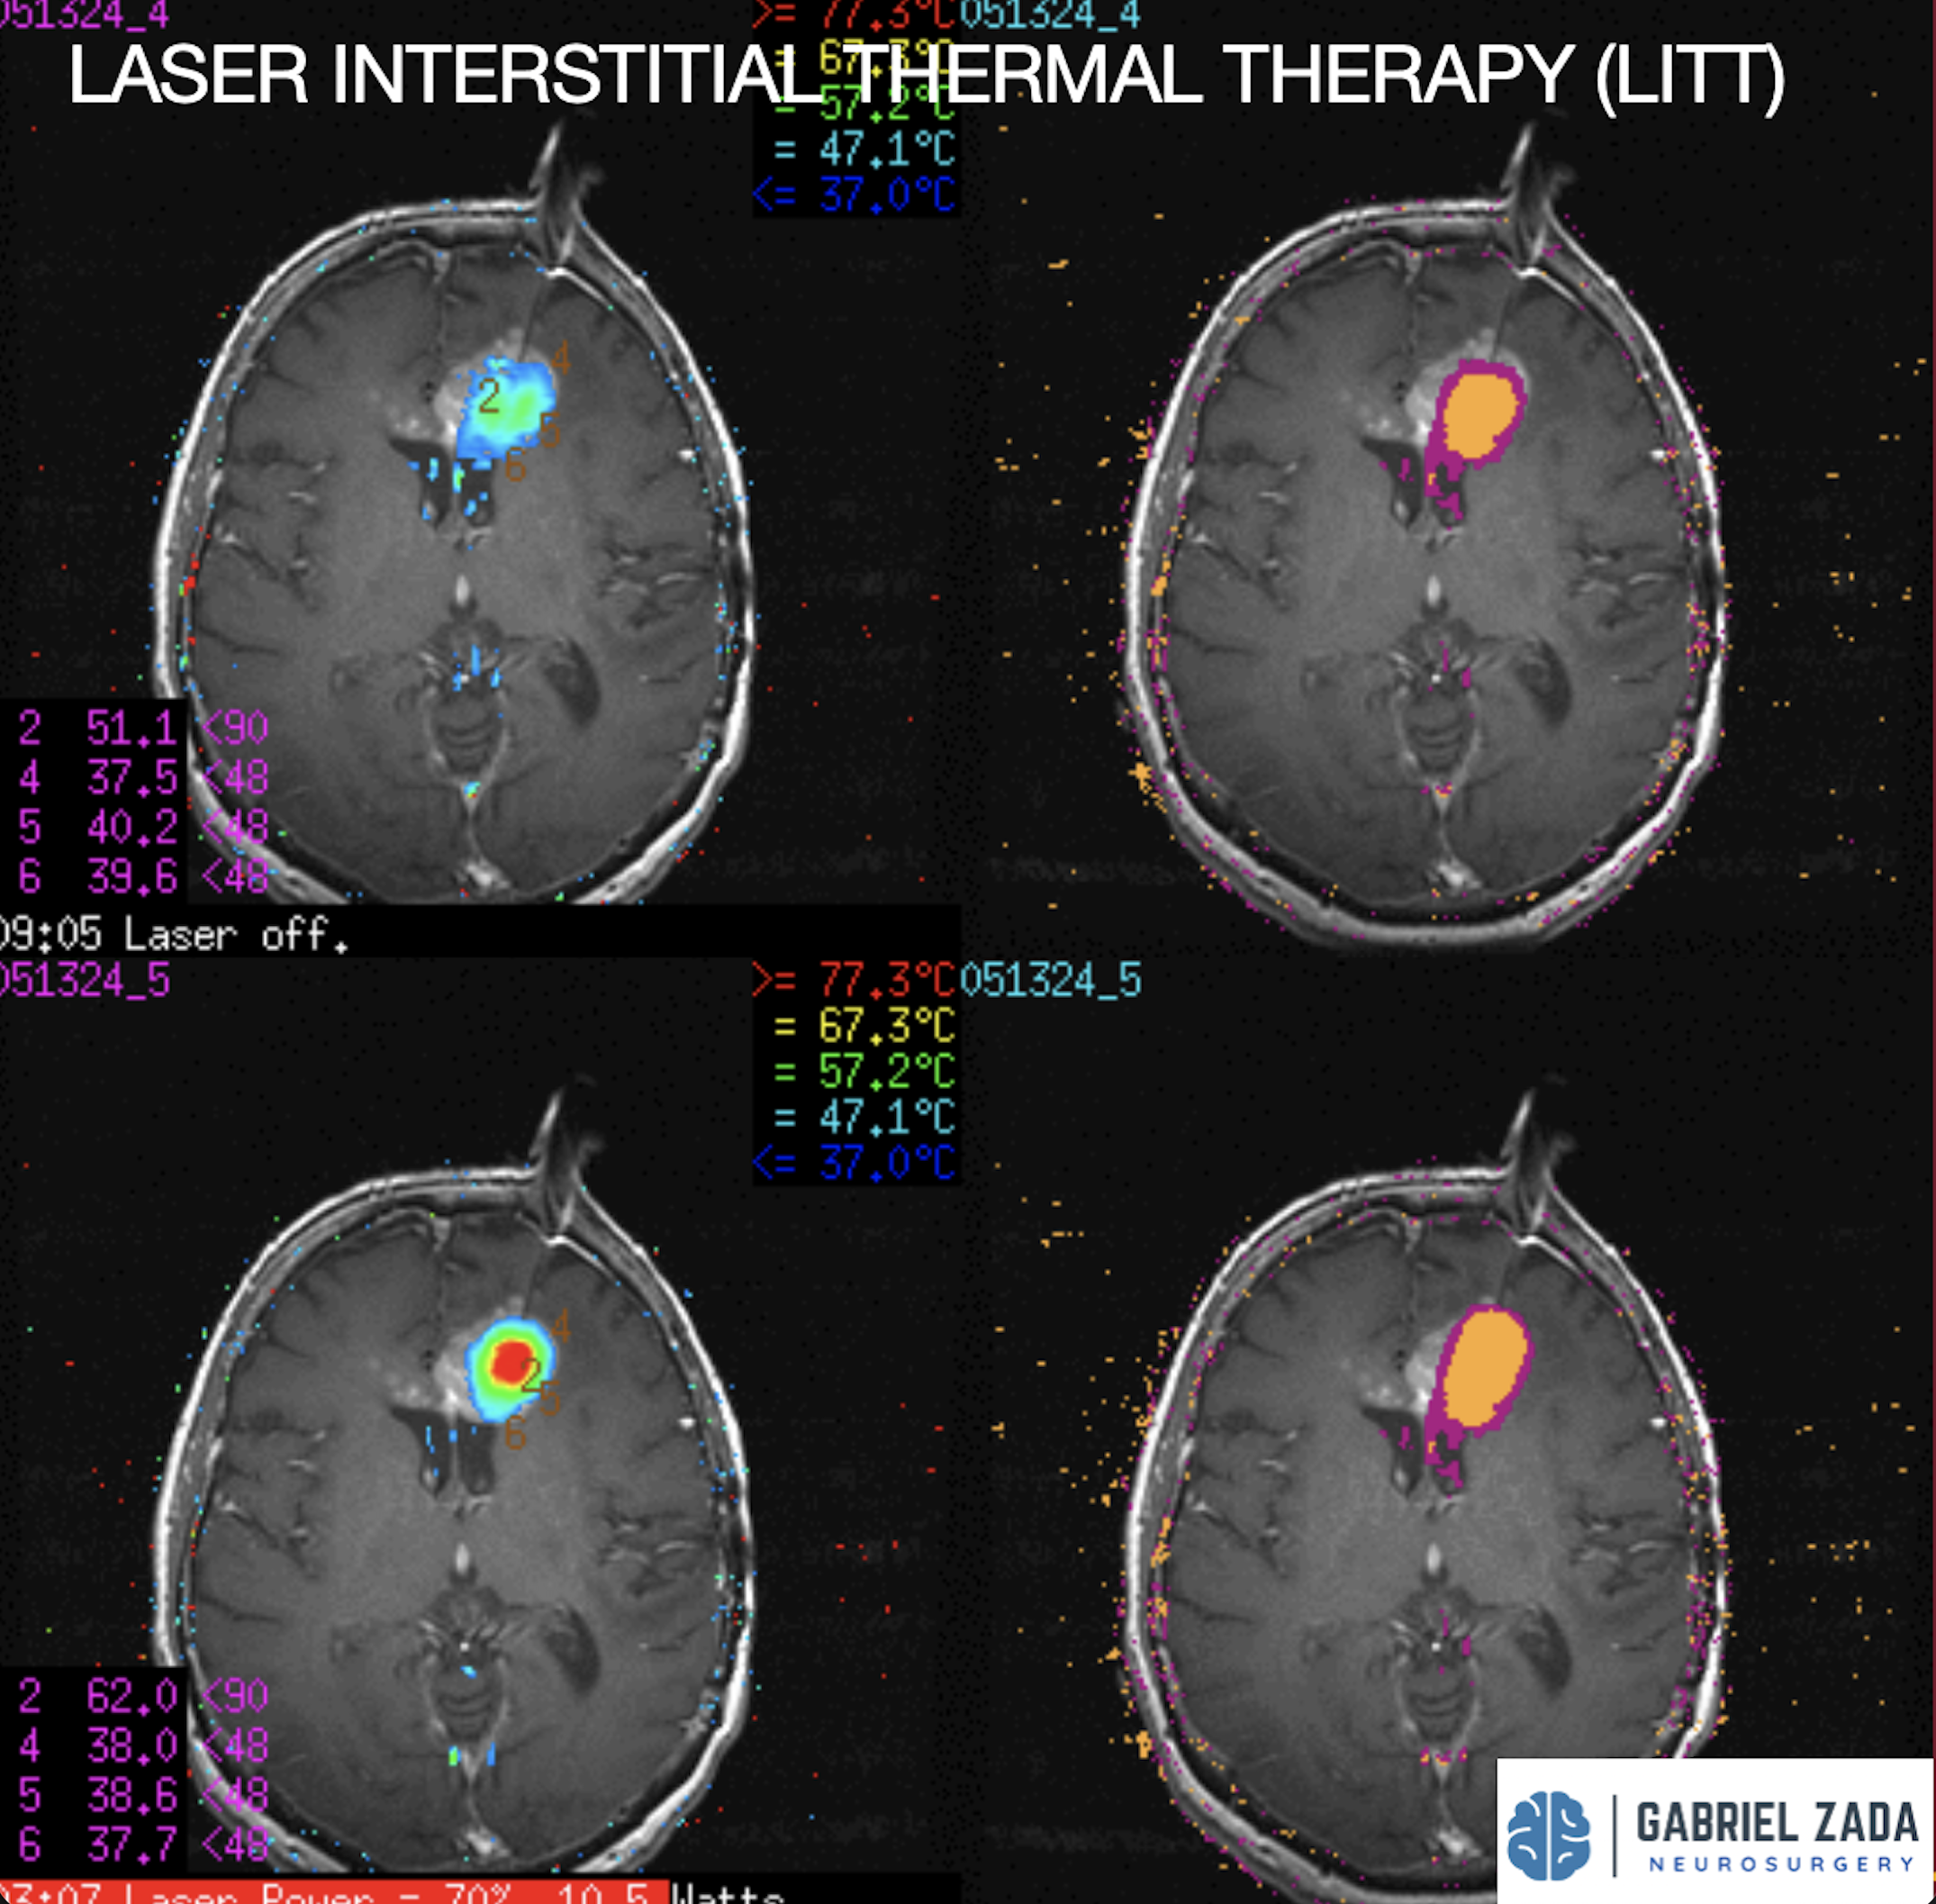

Explore this comprehensive gallery featuring pre‑ and post‑operative imaging of patients with skull‑base tumors treated by Gabriel Zada, MD, MS, FAANS, FACS. These cases highlight Dr. Zada’s expertise in advanced neurosurgical techniques and outcomes.

*Representative cases shown for educational purposes. All images de-identified. Individual results vary.